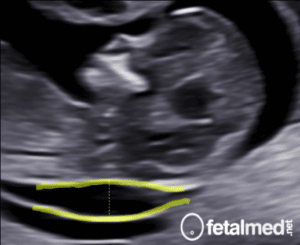

Seu bebê pesa cerca de 580 gramas agora. Mede cerca de 27 cm da cabeça aos pés. O corpo torna-se mais proporcional a cada dia e os ossos do ouvido médio começam a endurecer, tornando possível a condução do som. O feto reconhece os sons maternos tais como a respiração, os batimentos cardíacos, a voz e a digestão.

Se nascer agora, seu bebê já tem chance de sobreviver, contudo o sistema respiratório ainda está em desenvolvimento. Esperamos que ele fique aí dentro por várias semanas!! Ossos, músculos e órgãos apresentam crescimento estável. Os vasos sanguíneos, ossos e órgãos são visíveis sob uma fina membrana de pele, rósea e enrugada.